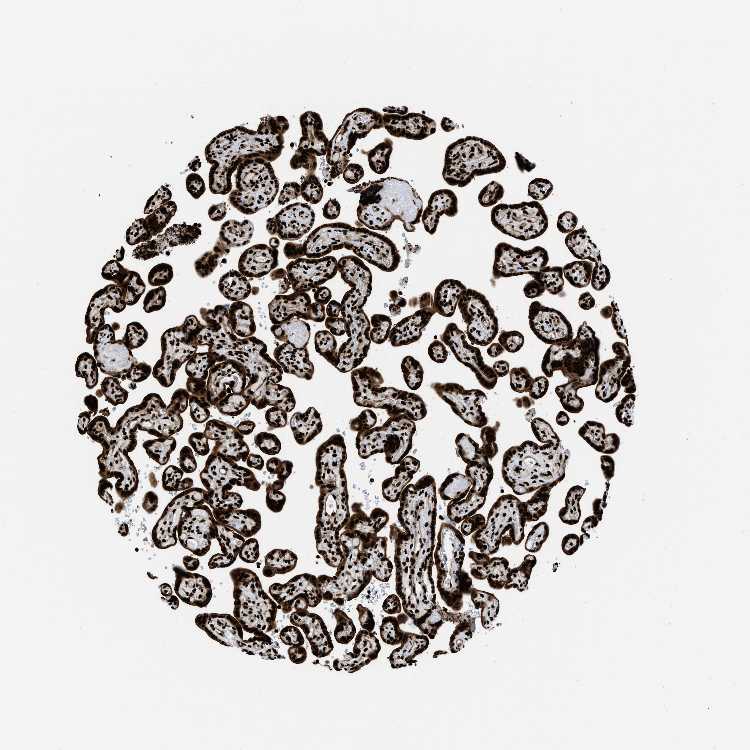

PLACENTA